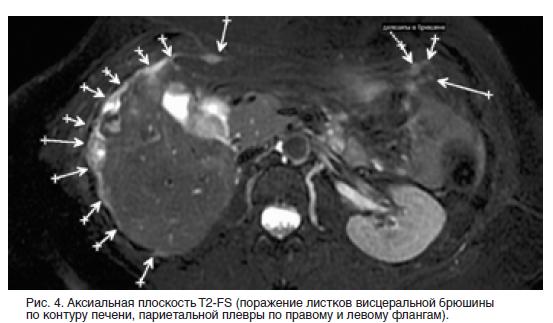

Канцероматоз таза

Канцероматоз таза 112 фото